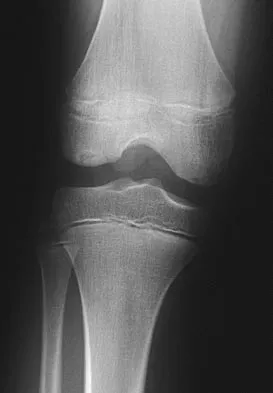

A 40-year-old woman reports the atraumatic onset of severe knee pain and swelling after undergoing an uncomplicated elective cholecystectomy 1 week ago. She denies any history of diabetes mellitus or HIV but has had occasional episodes of mild knee pain and swelling that have always responded to nonsteroidal anti-inflammatory drugs. Radiographs are shown in Figures 5a and 5b. A knee aspiration yields a WBC count of 35,000/mm3. The aspirate should also yield which of the following findings?

Explanation

The radiographs reveal chondrocalcinosis of the menisci. This is caused by calcium pyrophosphate crystals, which are weakly positive birefringent rhomboid-shaped crystals. Frequently, this condition is asymptomatic; however, routine abdominal surgery may cause precipitation of these crystals and pain. Gout, which is caused by strongly negative birefringent needle-shaped sodium urate crystals, is not associated with chondrocalcinosis and is rare in younger women. Gross blood is uncommon without trauma. Infection is not likely in a healthy patient who underwent uncomplicated surgery. Fisseler-Eckhoff A, Muller KM: Arthroscopy and chondrocalcinosis. Arthroscopy 1992;8:98-104.